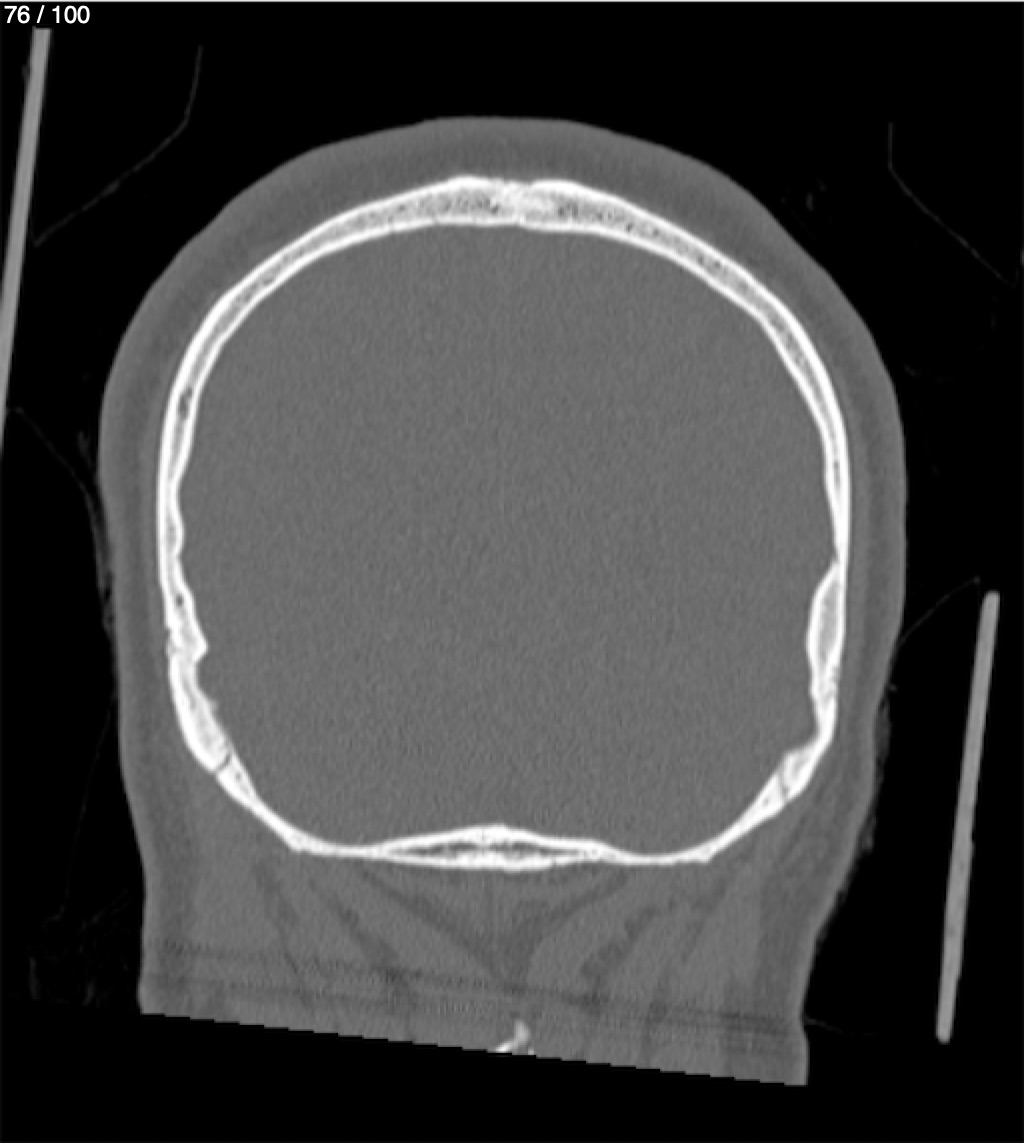

Reybet Garcia Fuentes 30A - T.C Craneo